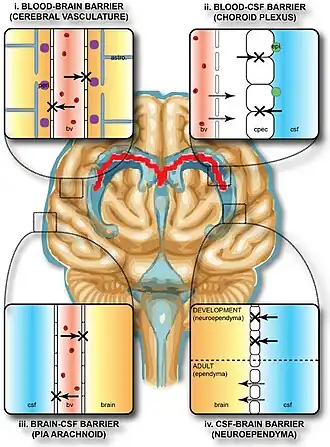

The blood–brain barrier (BBB) is a highly selective semipermeable border of endothelial cells that regulates the transfer of solutes and chemicals between the circulatory system and the central nervous system, thus protecting the brain from harmful or unwanted substances in the blood.[1] The blood–brain barrier is formed by endothelial cells of the capillary wall, astrocyte end-feet ensheathing the capillary, and pericytes embedded in the capillary basement membrane.[2] This system allows the passage of some small molecules by passive diffusion, as well as the selective and active transport of various nutrients, ions, organic anions, and macromolecules such as glucose and amino acids that are crucial to neural function.[3]

The blood–brain barrier restricts the passage of pathogens, the diffusion of solutes in the blood, and large or hydrophilic molecules into the cerebrospinal fluid, while allowing the diffusion of hydrophobic molecules (O2, CO2, hormones) and small non-polar molecules.[4][5] Cells of the barrier actively transport metabolic products such as glucose across the barrier using specific transport proteins.[6] The barrier also restricts the passage of peripheral immune factors, like signaling molecules, antibodies, and immune cells, into the central nervous system, thus insulating the brain from damage due to peripheral immune events.[7]

The BBB results from the selectivity of the tight junctions between the endothelial cells of brain capillaries, restricting the passage of solutes.[1] At the interface between blood and the brain, endothelial cells are adjoined continuously by these tight junctions, which are composed of smaller subunits of transmembrane proteins, such as occludin, claudins (such as Claudin-5), junctional adhesion molecule (such as JAM-A).[6] Each of these tight junction proteins is stabilized to the endothelial cell membrane by another protein complex that includes scaffolding proteins such as tight junction protein 1 (ZO1) and associated proteins.[6]

The BBB is composed of endothelial cells restricting passage of substances from the blood more selectively than endothelial cells of capillaries elsewhere in the body. Astrocyte cell projections called astrocytic feet (also known as "glia limitans") surround the endothelial cells of the BBB, providing biochemical support to those cells.[9] The BBB is distinct from the quite similar blood-cerebrospinal fluid barrier, which is a function of the choroidal cells of the choroid plexus, and from the blood-retinal barrier, which can be considered a part of the whole realm of such barriers.[10]